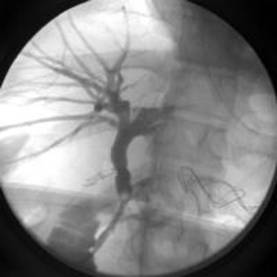

Colangiografia rimane il criterio standard per la rilevazione dei calcoli coledociti. Nel passato era disponibile solamente la colangiografia venosa, ma aveva una bassa sensibilità e precisione ed era gravata da effetti collaterali di tipo allergico. Con l'introduzione dell'ERCP e della colangiografia trans epatica e cutanea la suddetta metodica è stata soppiantata. L'ERCP è stata introdotta nei primi anni '70 ed è immediatamente diventata strumento diagnostico e terapeutico di scelta nei pazienti portatori di coledoco litiasi. A paziente premeditato con sedativi e anticoligernici (onde inibire reazioni vagali e ridurre tono e cinesi gastro-duodenale), si introduce per via orofaringea un apposito endoscopio a visione laterale, la cui estremità viene posizionata nella seconda porzione duodenale al davanti della papilla di Vater. Quest'ultima è incanalata ortogonalmente mediante apposita cannula inserita nei canali di servizio dell'endoscopio e orientabile dall'esterno. Si inietta quindi a bassa pressione, sotto controllo radioscopico, un MdC uro angiografico diluito, previo cateterismo, nel coledoco. Si assumono infine radiogrammi mirati, a paziente supino e prono, nelle proiezioni più idonee a documentare il sistema duttale dei dotti biliari. La percentuale di successo nell'incannulazione della via biliare principale, in mani esperte è superiore al 90%.Le complicanze, costituite da: emorragie, pancreatite acute iatrogene, colangiti, lesioni strumentali e reazioni a farmaci incidono in ragione di circa il 3% dei casi. 23

Fig5- esame col angiografico- notevole dilatazione della via biliare principale e immagine di minus riferibile a formazione litiasica nel coledoco

Fig 6- ERCP